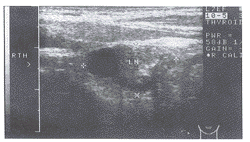

2、正常淋巴结组30例, 计120个正常浅表淋巴结,声像图呈梭形, 最大一个淋巴结长径19mm, 淋巴结以腹股沟部较大,淋巴结髓质回声稍强于皮质, CDFI显示淋巴结门髓质部干状血流信号(图1),DPI则更为敏感。

图1 颈部正常淋巴结呈梭形,门髓质血流显示